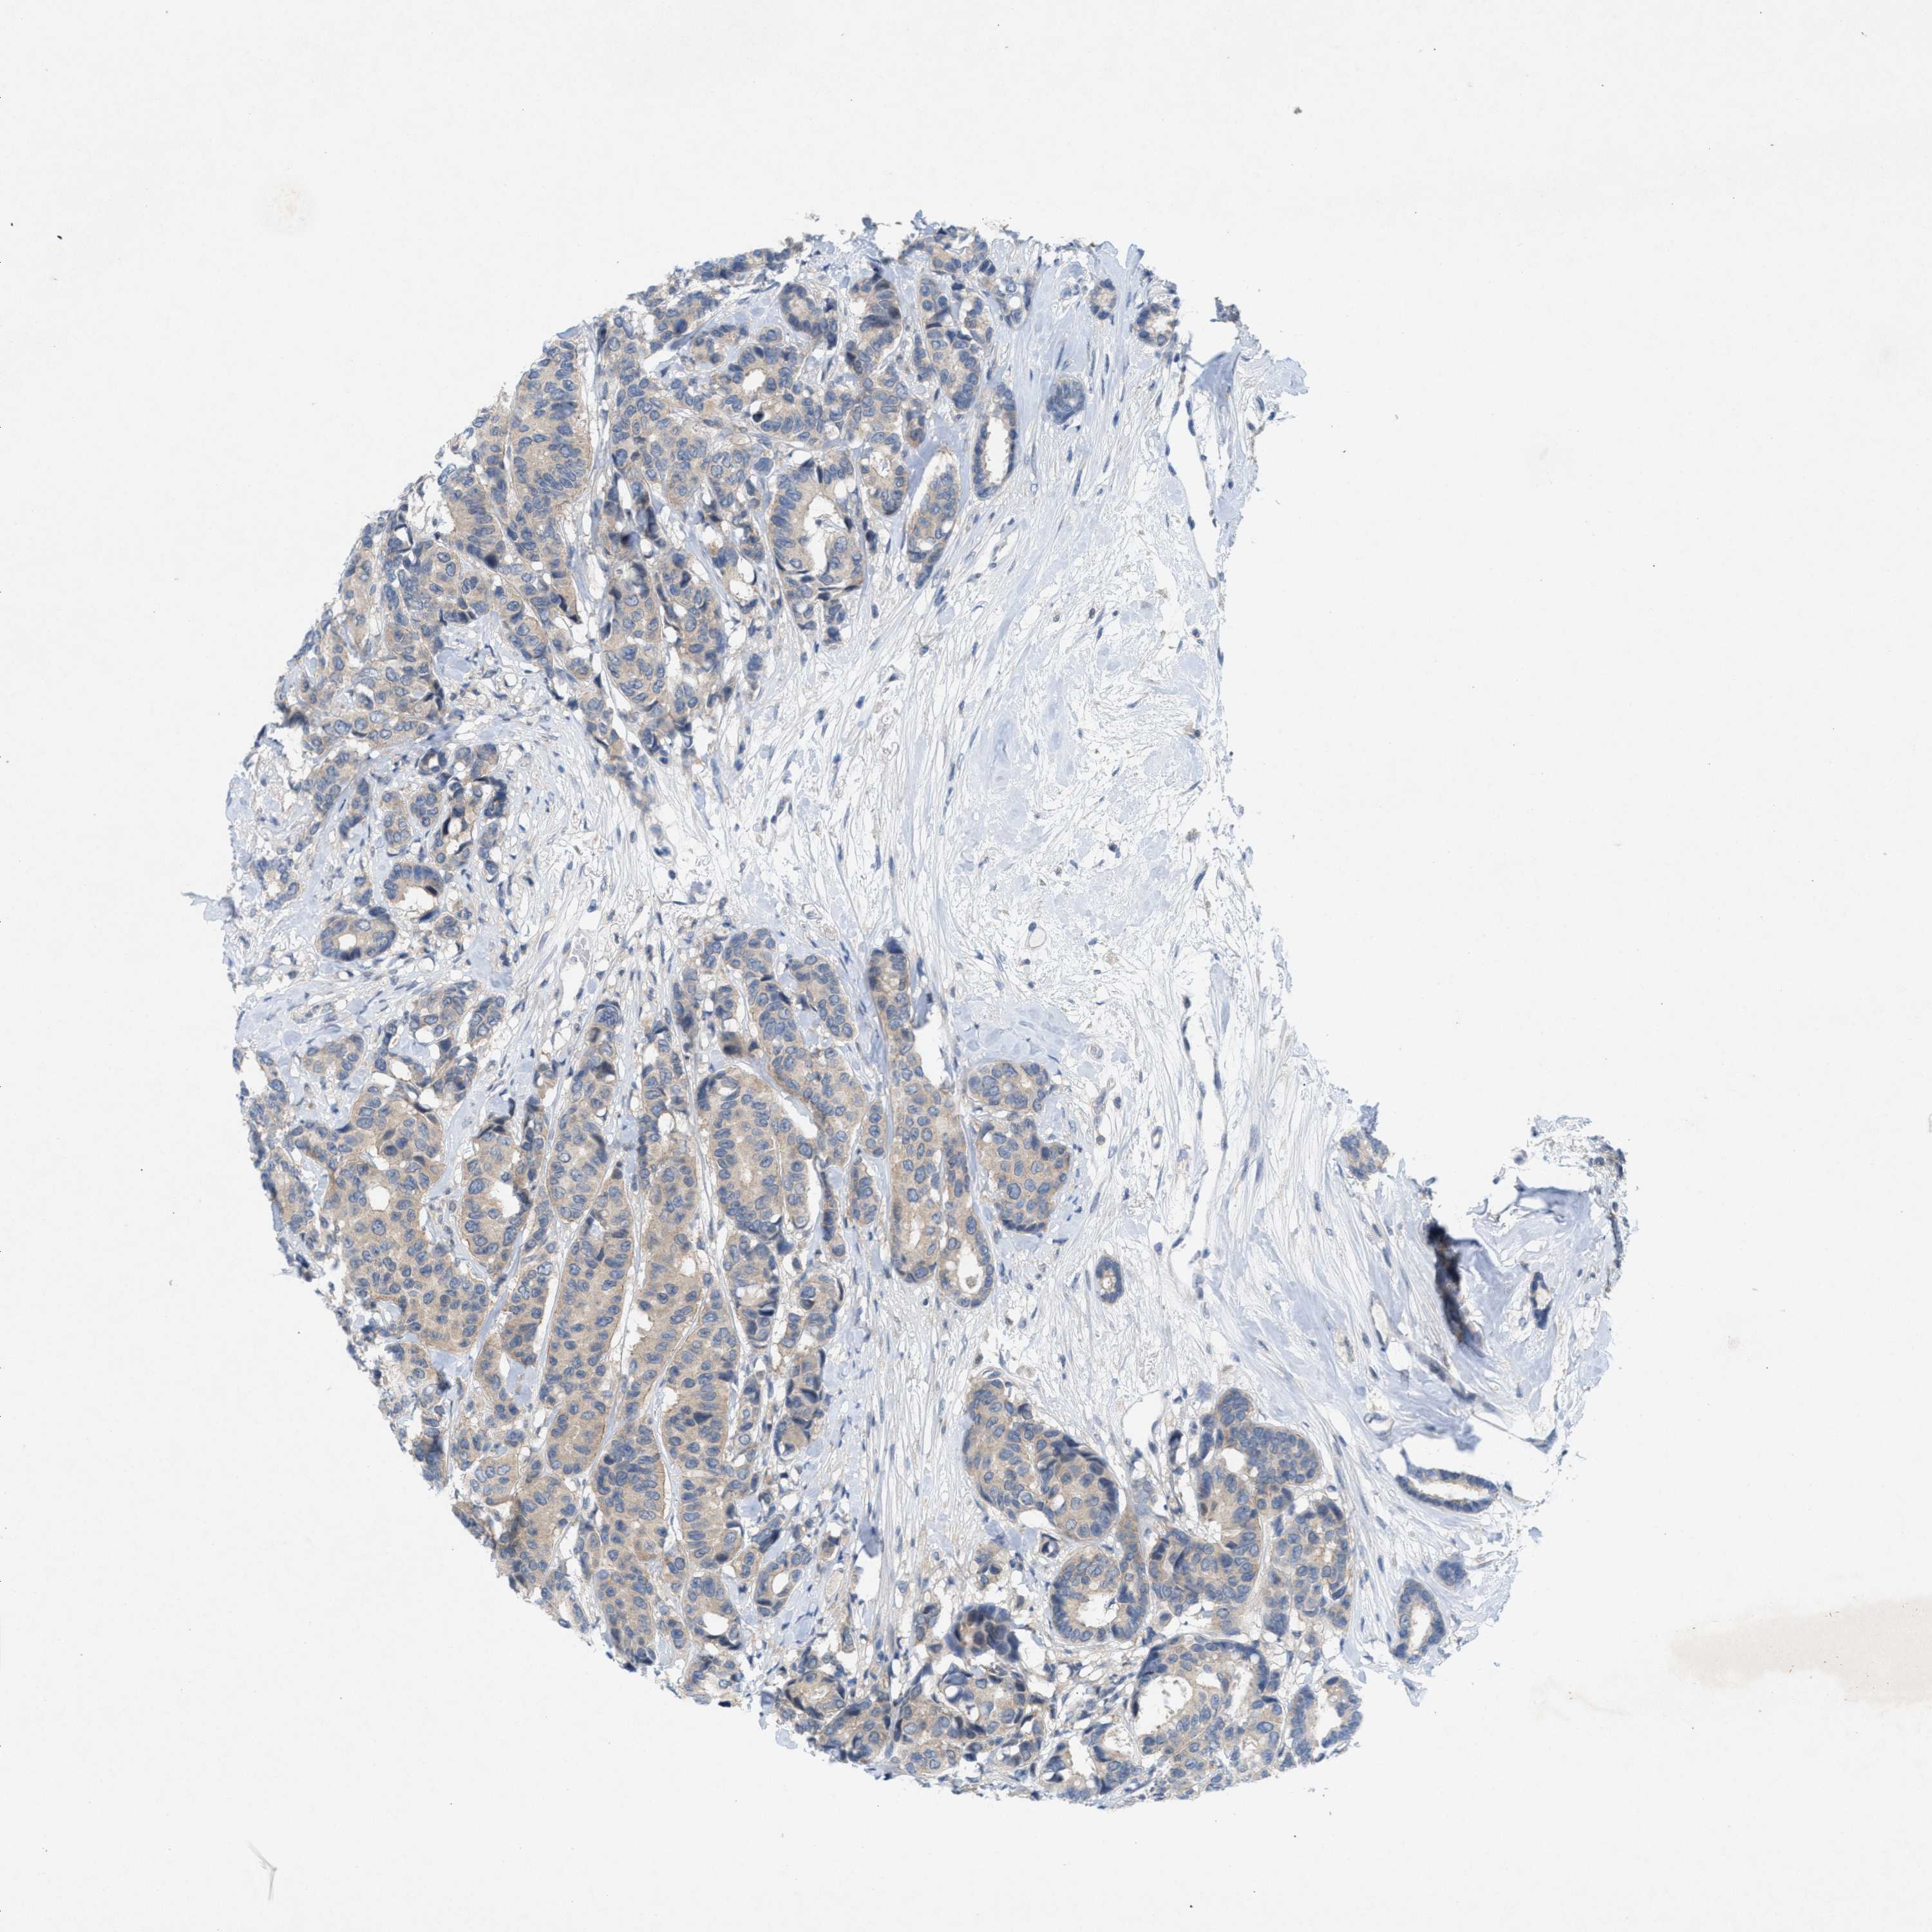

CANCER BREAST CANCER Show tissue menu

BRCA TCGA BRCA VALIDATION PROTEIN EXPRESSION